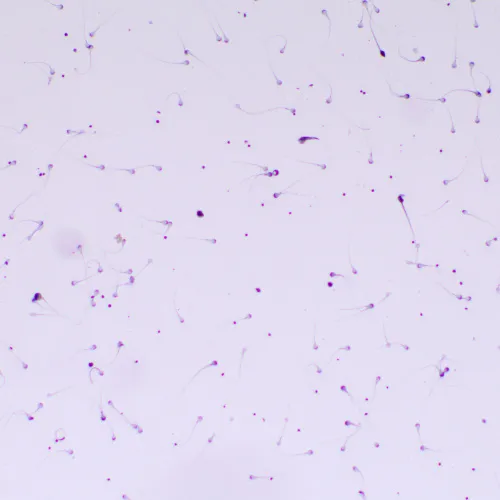

Микроскоп MAGUS Bio 260T – рутинная модель, которая оснащена интеллектуальным освещением, встроенным ЖК-экраном и может дополняться компонентами, которые расширят возможности микроскопа для работы в темном поле, с фазовым контрастом, в люминесцентном свете или с применением поляризации.

В базовой комплектации микроскоп работает в светлом поле с прозрачными и полупрозрачными тонкими биологическими препаратами. Может применяться в лабораториях и научных учреждениях для рутинных исследований, для обучения молодых специалистов.

- В базовой комплектации микроскоп предназначен для исследования биологических образцов в светлом поле в проходящем свете